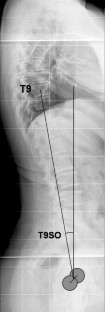

Fig. 3

Fig. 4